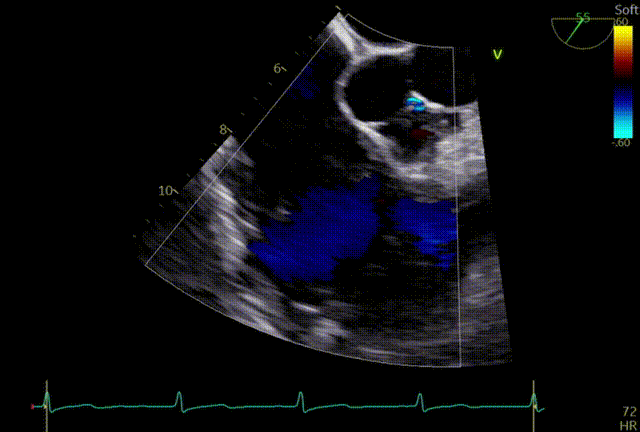

术前TTE:三尖瓣重度反流

入院经胸心脏彩超诊断:1、重度三尖瓣关闭不全(TR 4+)。2、双房右室扩大,以右心扩大为著;升主动脉及肺动脉增宽。3、左室壁整体运动不协调。4、轻度二尖瓣反流;轻度主动脉反流。5、左室整体收缩功能正常。6、右室壁收缩功能减低。